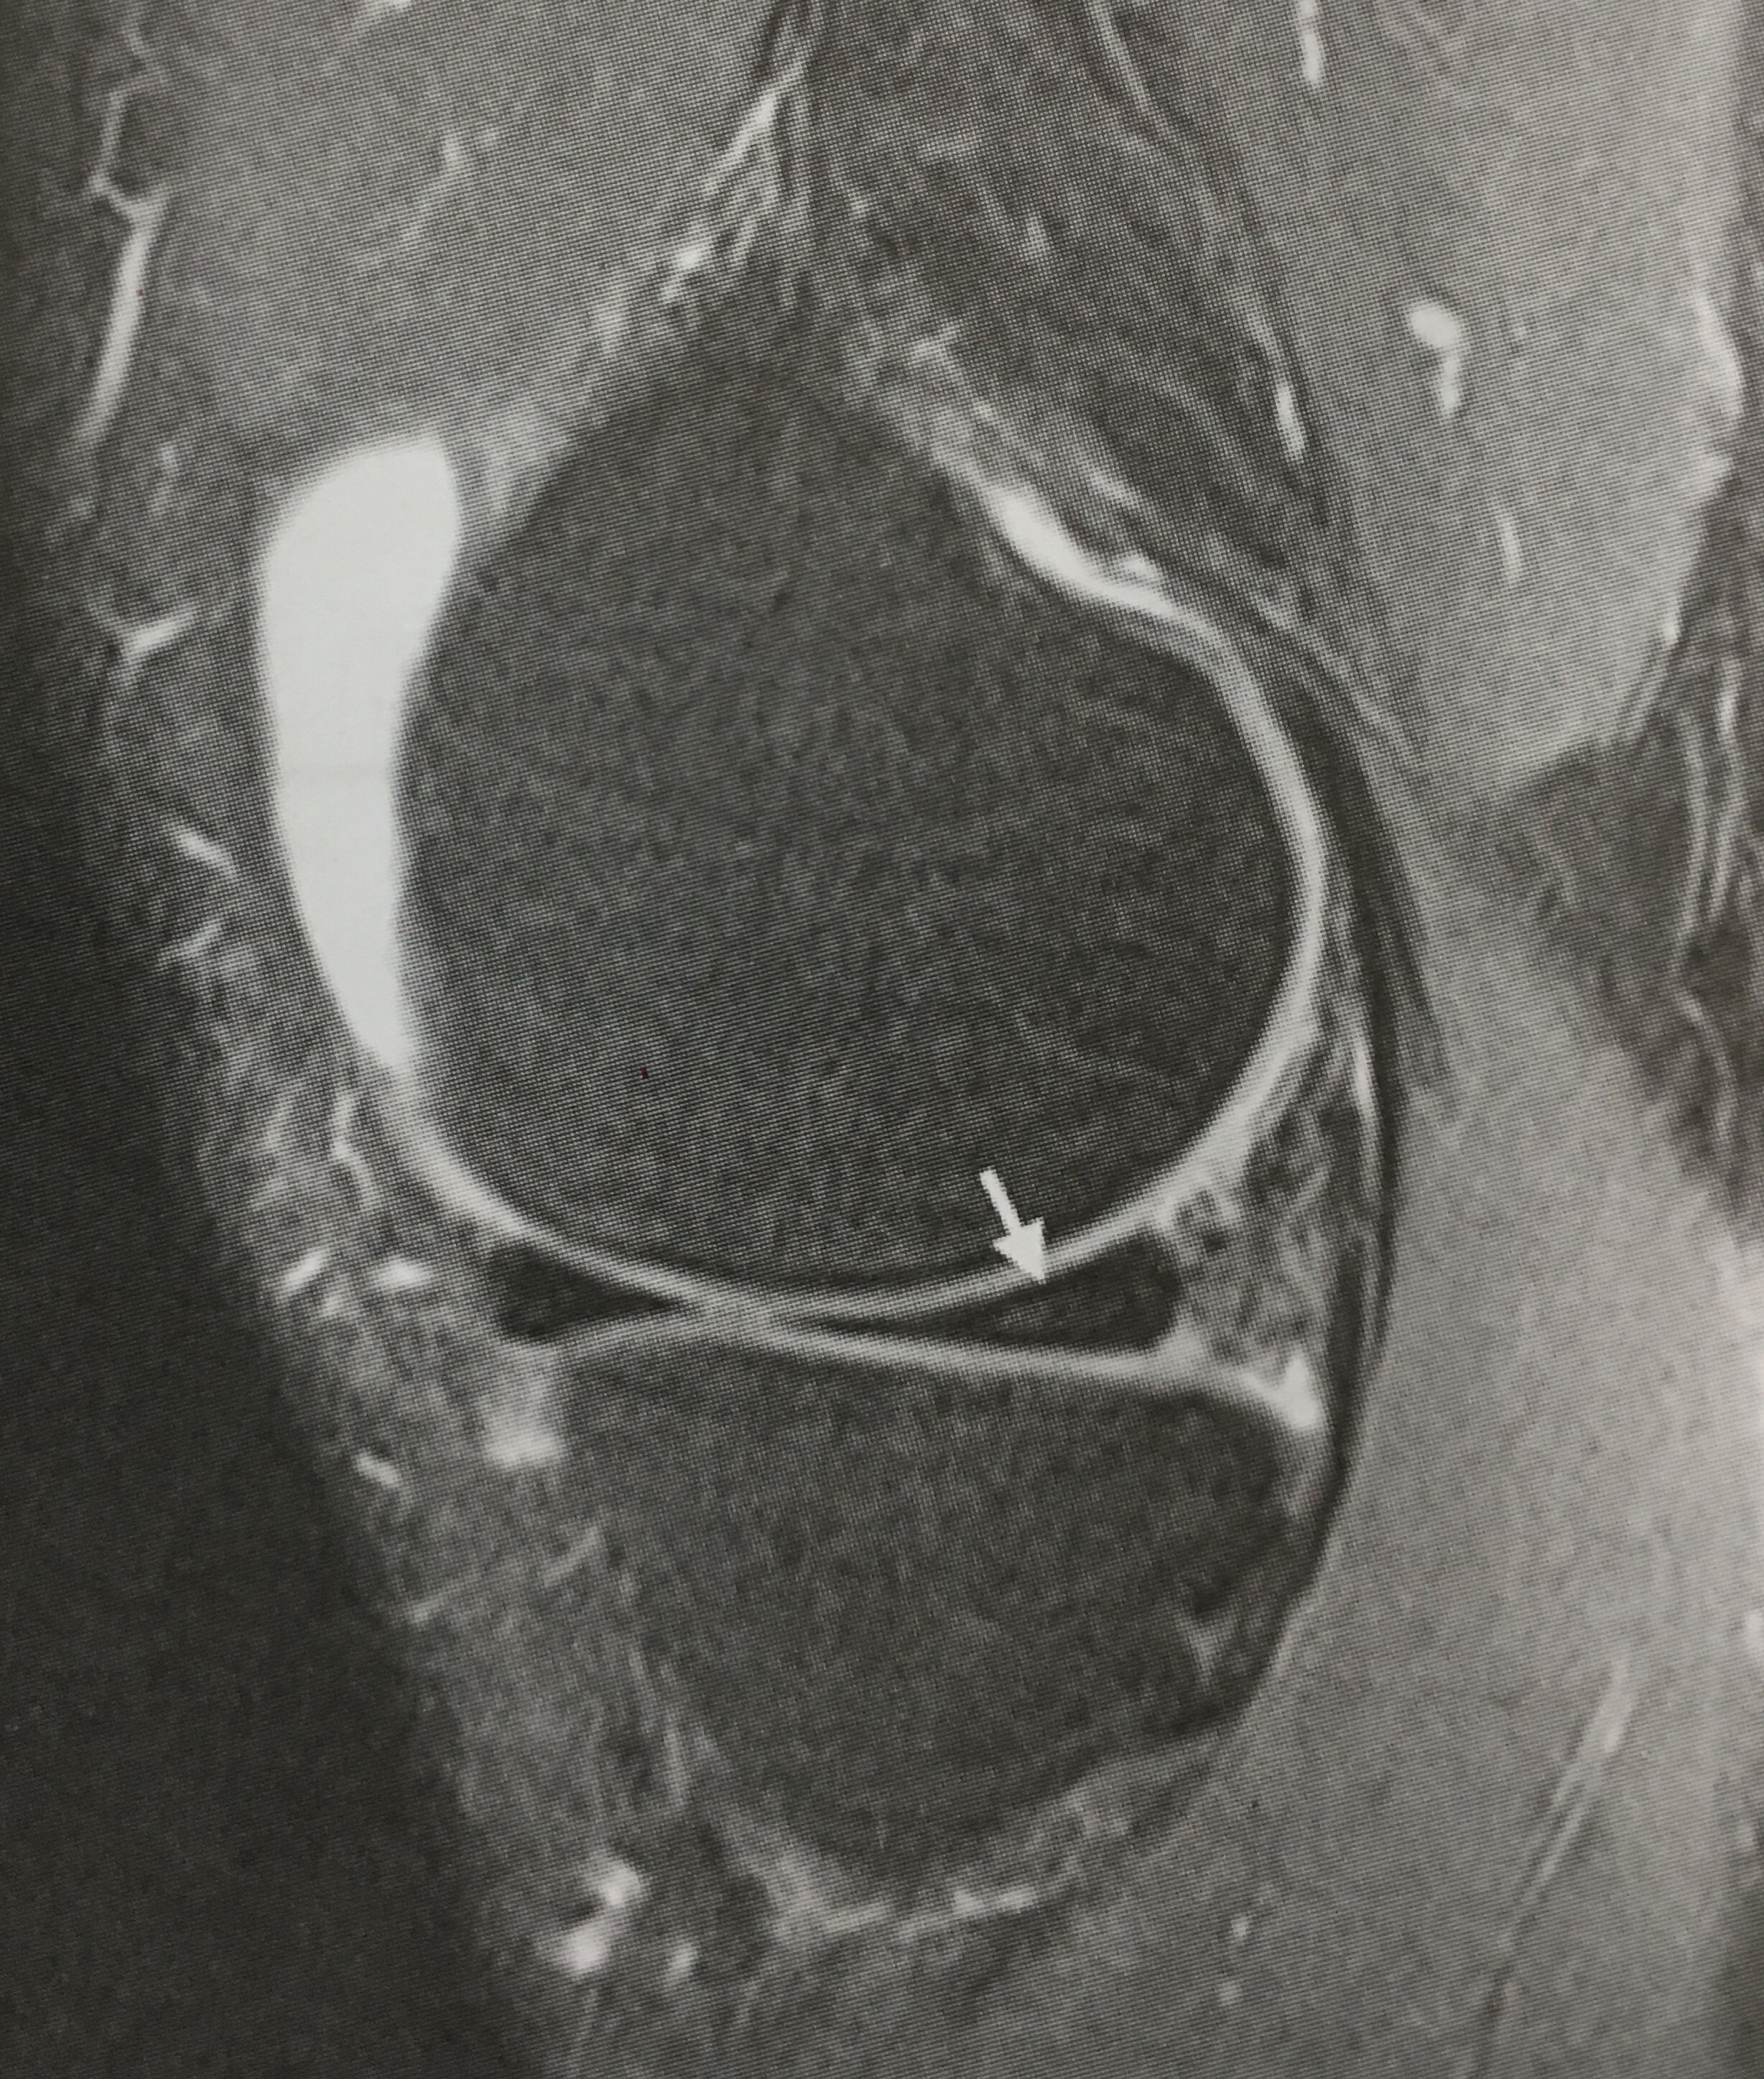

内侧半月板损伤图片

膝关节内侧半月板损伤病例

【半月板】半月板损伤的mri诊断

半月板损伤.jpg